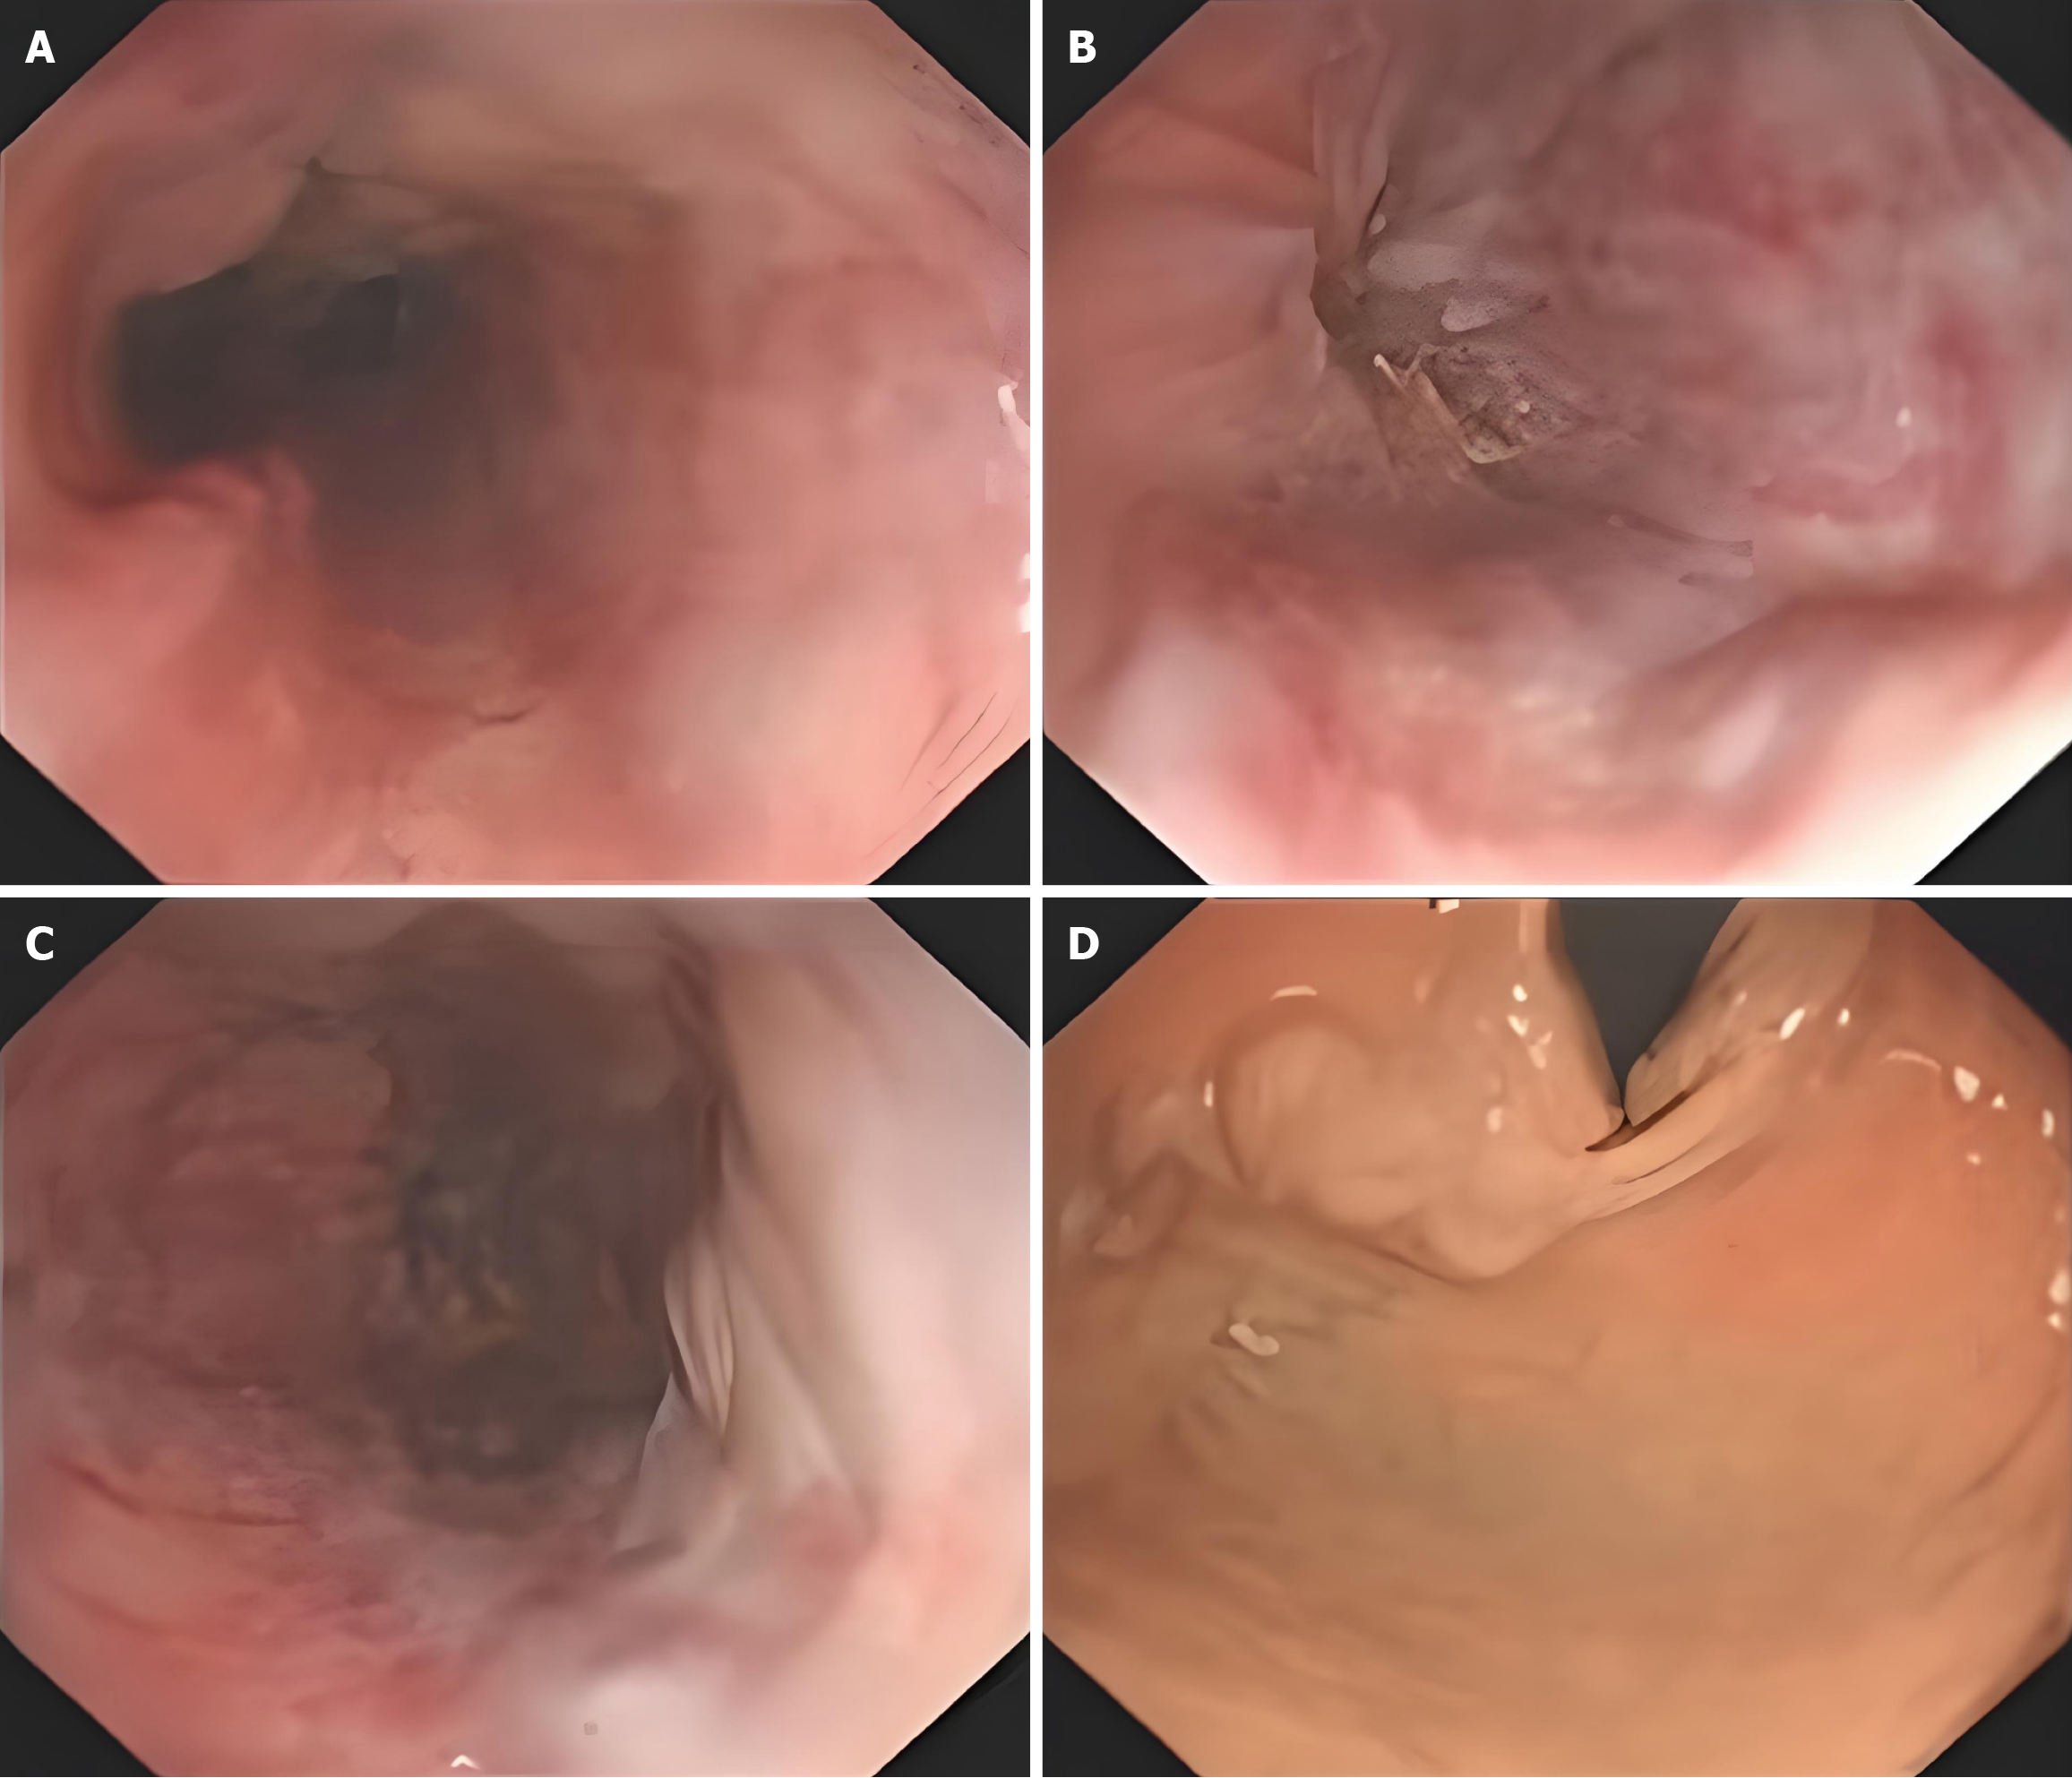

Gastroscopy examination showed severe varices in the mid and lower esophageal segments and gastric fundus, indicating portal hypertension-related gastric disease (Figure 1). Abdominal computed tomography (CT) examination revealed cirrhosis, splenomegaly, portal hypertension with collateral circulation formation, and a small amount of mural thrombosis in the main portal vein, superior mesenteric vein, and splenic vein (Figure 2).